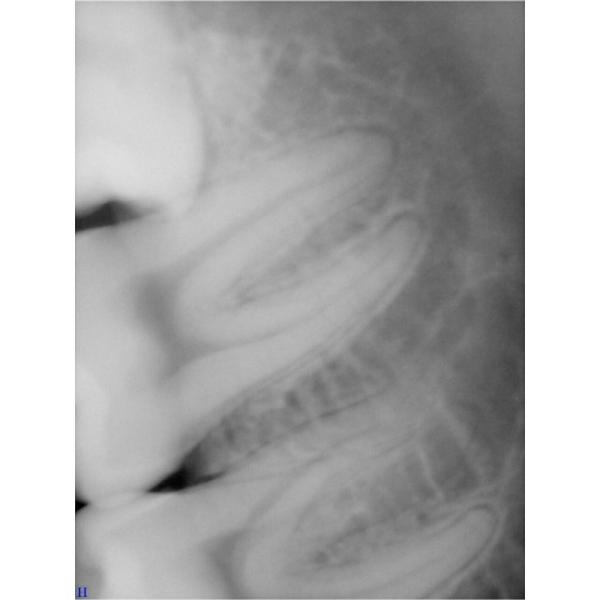

MCX-12C is the minimum size hand and portable dental X ray machine. It uses micro power, micro focus, micro exposure. In non-working area, there almost are not X ray light. So it is very safety for the doctor and also safety for the patients. It can be controlled by remote, too. The picture is high quality.

High quality pictures

High Frequency Dental Clinic Equipments Hand Held Dental X Ray Machine Images |